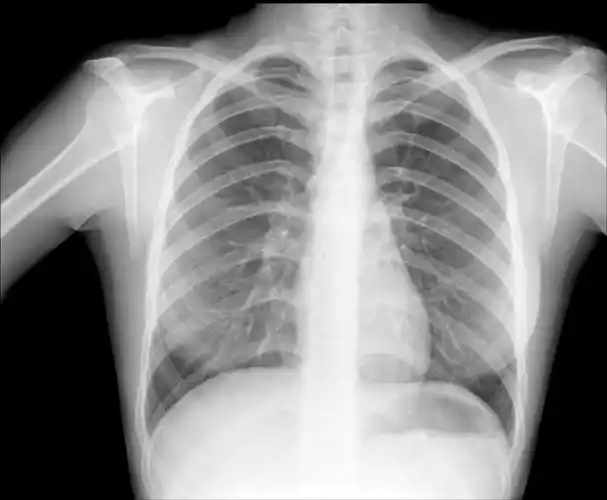

这张胸片肺部有问题吗?

影像诊断报告里"肺纹理增多"到底是个什么鬼?

正常胸片及其需要牢记的正常结构:天天师兄说明